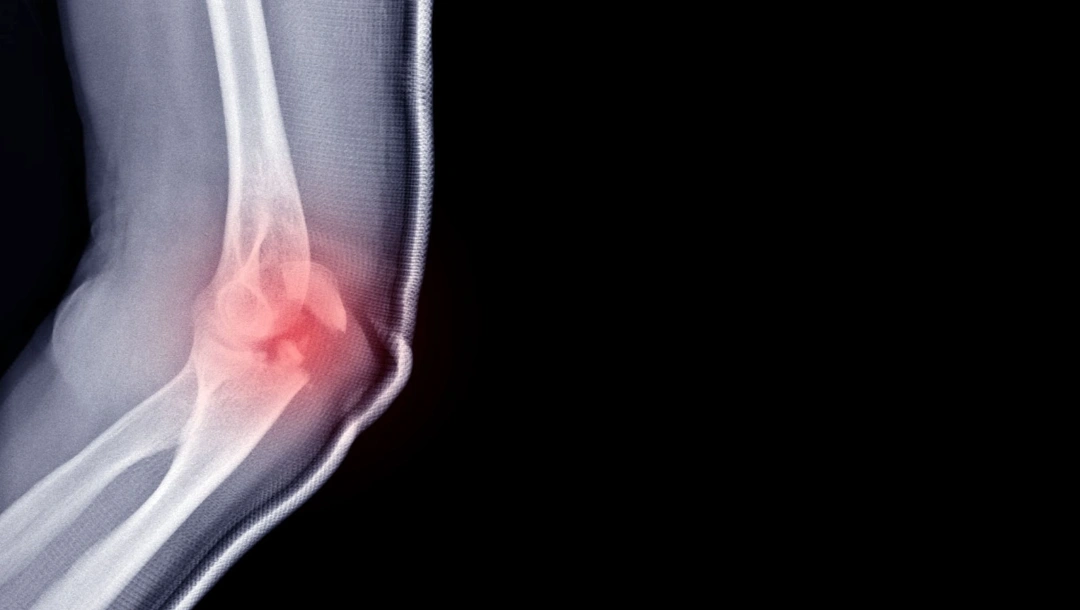

An elbow fracture refers to a break in one or more of the bones that form the elbow joint — the humerus (upper arm bone), radius, or ulna (forearm bones). Because the elbow is a complex hinge joint that allows both bending and rotation of the forearm, a fracture can significantly affect arm movement and daily function.

- X-ray imaging — standard X-rays are the primary investigation method for suspected fractures. They reveal the location, type and severity of the break, and help determine whether the bones are displaced or involve the joint surface.